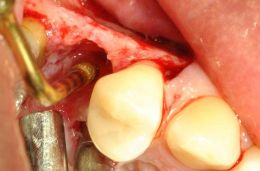

FRAZIONE RADICOLARE CON PUNTA ARIANE-Z SU TURBINA, POI COMPLETATA CON OT7S-3

FRAZONE COMPLETATA

DOPO RIMOZIONE DEL SEGMENTO PALATINO, LA PORZIONE VESTIBOLAre viene spinta senza appoggiarsi alla corticale esterna ma lavorando dai due versanti prossimali verso il vuoto creato palatalmente

frammenti estratti, si noti la severa uncinatura apicale di quello vestibolare (a sn)